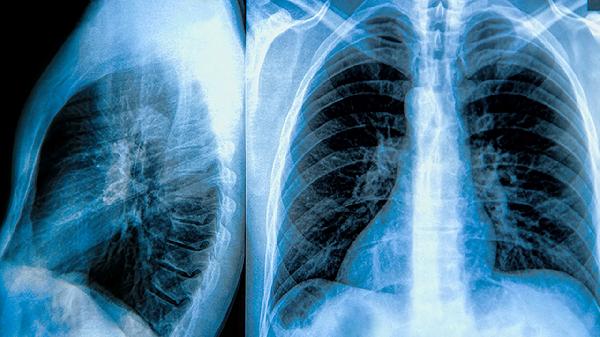

肺大泡患者是否需要手术主要取决于肺大泡的大小、数量、位置以及是否出现并发症。肺大泡直径超过5厘米、反复发生气胸、合并感染或严重影响肺功能时通常建议手术治疗。手术方式主要有肺大泡切除术、肺减容术、胸腔镜手术等。